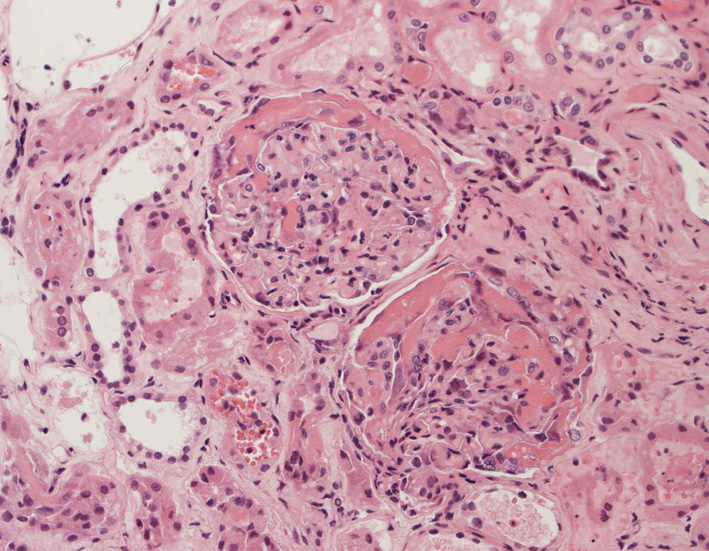

76歳男性 (Post mortum needle examination -- lung, kidney )

腎臓の病理組織所見-->壊死性糸球体腎炎

kidney01.jpg

kidney02.jpg

kidney03.jpg

Fig.01Fig.02Fig.03

kidney04pas.jpg

kidney05.jpg

kidney06.jpg

Fig.03(PAS)Fig.04(PAM染色)Fig.05(PAM染色)

kidney07.jpg

kidney08.jpg

Fig.06Fig.07 尿細管壊死